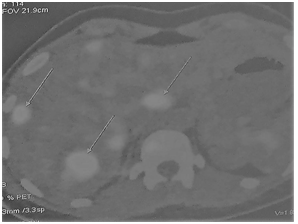

She received preoperative systemic chemotherapyassociated with target therapy. The scheme was the following: docetaxel and carboplatin associated with both trastuzumab and pertuzumab. She received six cycles with partial response of both primary lesion and hepatic metastases (Figure 1–PET-Scan). This way,we proposed a “first-liver approach” because it was observed a good response after systemic therapy besides that she was a healthy young woman. She underwent an open right hepatectomyand caudate lobectomy with atypical resection of three small lesions into left lobe. She was carried out at fifth postoperative day without any complication. Pathological evaluation showed only both fibrosis and necrosis in hepatic lesions. It was considered complete histological response. Subsequently, shereceived four more cycles of the same initial scheme (except carboplatin). There was maintenance of the response in primarytumor andshe was finally submitted to radical mastectomy with selective axillar lymphadenectomy. Pathological evaluationevidenced absence of microscopic residual tumor(complete pathogicalresponse). Since that time sheisreceiving only bothtrastuzumabandpertuzumab. To date, thirty months after hepatic resection,she is alive without any recurrence (Figure 2–PET-Scan). She presents a very good quality of her life.

Figure 1 PET-Scanafter initial treatment –bilateral hepatic metastases.